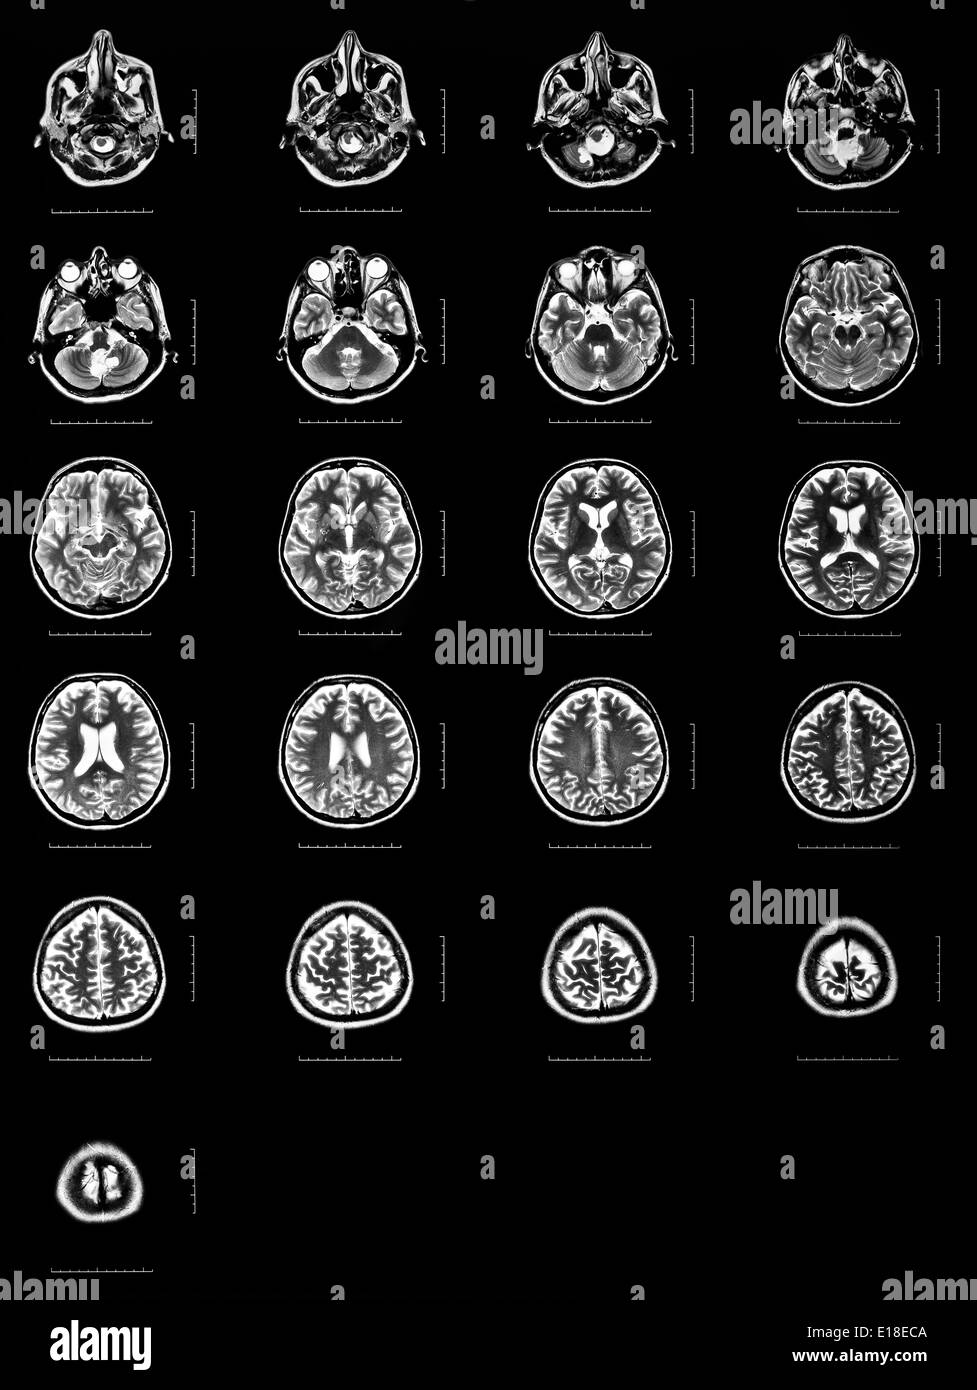

Séquence des sections horizontales d'un cerveau humain - IRM Banque D'Imageshttps://www.alamyimages.fr/image-license-details/?v=1https://www.alamyimages.fr/sequence-des-sections-horizontales-d-un-cerveau-humain-irm-image69643066.html

Séquence des sections horizontales d'un cerveau humain - IRM Banque D'Imageshttps://www.alamyimages.fr/image-license-details/?v=1https://www.alamyimages.fr/sequence-des-sections-horizontales-d-un-cerveau-humain-irm-image69643066.htmlRFE18ECA–Séquence des sections horizontales d'un cerveau humain - IRM